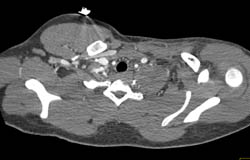

Diagnosis

Avascular Necrosis (AVN) Left Femoral Head